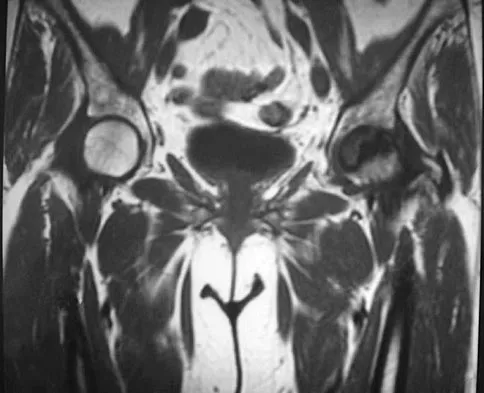

Question 73

A 65-year-old man with ankylosing spondylitis has neck pain after falling back over his lawnmower, striking his thoracic spine, and forcing his neck into extension. Examination reveals subtle weakness of the intrinsics and finger flexors at approximately 4+/5. Initial management consists of immobilization in a rigid collar, and placing his head in the anatomic position. Radiographs reveal a subtle extension fracture of the lower cervical spine. Approximately 6 hours after the injury, he reports increasing paresthesias in his upper and lower extremities, and examination now shows his intrinsics are 2/5, finger flexors are 3/5, and his triceps are now weak at 4/5 on manual motor testing. In addition, his lower extremities now show weakness in both dorsal and plantar flexion of the ankle in the range of 4/5. Repeat radiographs appear unchanged. An MRI scan is shown in Figure 2. Management should now consist of

Explanation